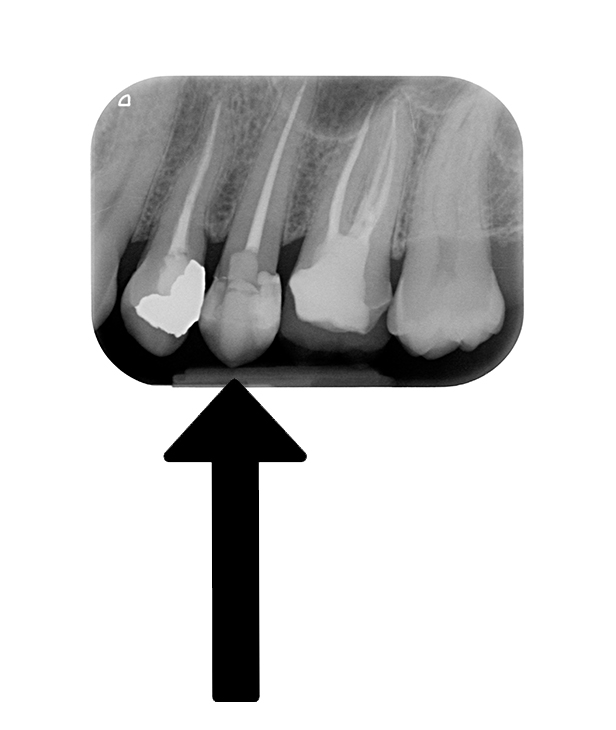

Eccolo qua:

L’intarsio su 2.6 è nostro (la cura canalare no!! Non ritrattato perchè non c’era lesione…).

Guarda l’incriminato: trattato endodonticamente, posteriore, NON PROTETTO e … otturato con 3 compositi diversi. Uno mesiale, uno distale uno per il buco della “canalizzazione”!